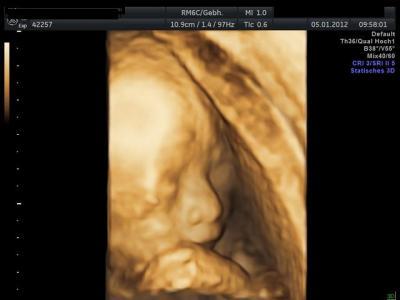

Hier auch mal ein Bild von unserer Maus allerdings aus der 21.ssw

man bin ich gespannt wie sie dann aussieht